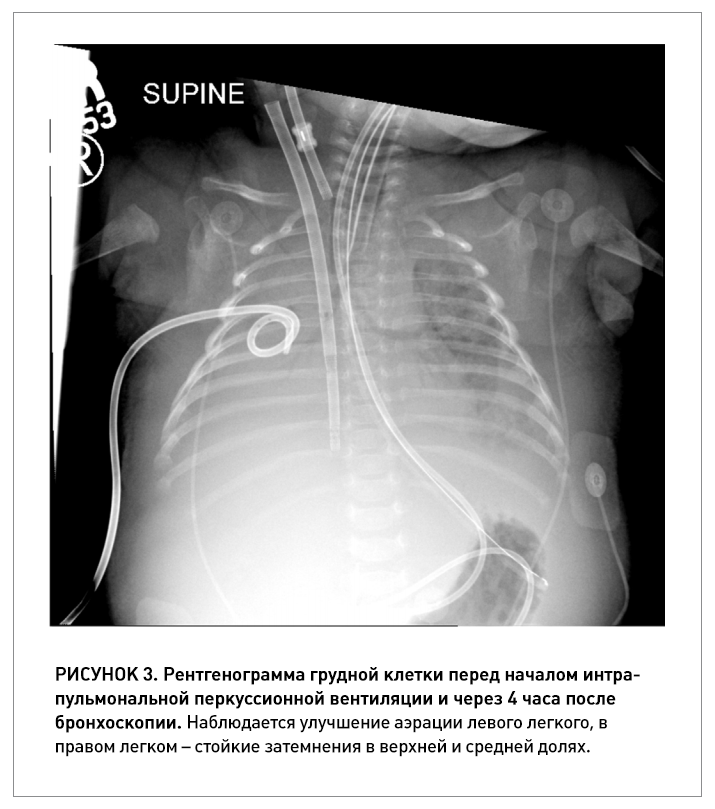

Мы представляем описание клинического случая младенца в возрасте 4 недель, у которого развилась тяжелая коклюшная инфекция, требующая ЭКМО.

Есть данные, что ассоциированная с COVID-19 пневмония характеризуется образованием большого количества очень густой и вязкой мокроты. Аппараты интрапульмональной перкуссионной вентиляции IPV Percussionaire давно зарекомендовали себя как эффективный и...

При коронавирусной инфекции SARS-CoV-2 стандартные технологии вентиляции не оправдали надежд и рекомендованы к применению только по жизненным показаниям. Альтернативой традиционной ИВЛ может стать интрапульмональная перкуссионная вентиляция легких.

В работе рассмотрены 3 клинических случая: пациенты, госпитализированные с COVID-пневмонией и тяжёлым острым респираторным синдромом, прошли курс процедур высокочастотной перкуссионной вентиляции (ВЧПВ). После ВЧПВ все пациенты демонстрировал...